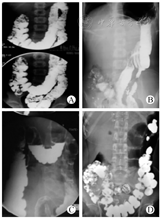

肠系造影检查为主要诊断方法,指征包括:横结肠冗长悬吊、甚至坠入盆腔,造影剂形成液平面;脾曲高悬,横结肠与降结肠间形成锐角,造影剂经过受阻;乙状结肠冗长,扭曲扩张,直肠无狭窄,可见粪便堆积;24 h复查造影剂排空障碍,残留于横结肠、乙状结肠及直肠(图1)。

所有患儿行肠系造影及排空检查,均可发现横结肠冗长悬垂坠入盆腔,脾曲高悬,横结肠与降结肠之间形成锐角,以及乙状结肠冗长扭曲、排空延迟的典型征象(图2)。